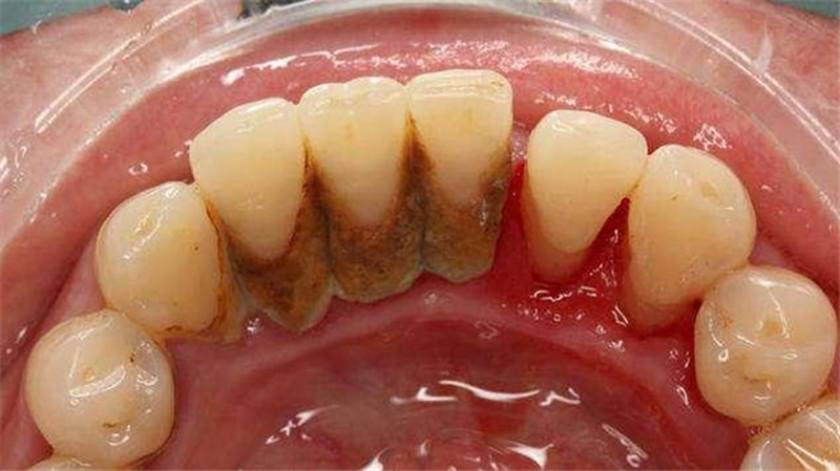

Nếu không được làm sạch hàng ngày, mảng bám sẽ bị vôi hóa theo thời gian bởi các thành phần khoáng hóa có trong nước bọt, tạo thành một lớp cứng có màu vàng hoặc nâu, bám chặt trên bề mặt răng, kẽ răng và sâu dưới nướu, gọi là vôi răng.

Vôi răng hình thành tạo điều kiện cho vi khuẩn tấn công răng

Vôi răng hình thành tạo điều kiện cho vi khuẩn sinh sôi và phát triển, chúng sẽ tấn công răng miệng, gây ra nhiều bệnh lý răng miệng như viêm nướu, viêm nha chu, sâu răng, viêm tủy răng, áp-xe răng.